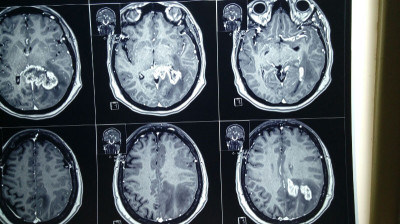

Paciente femenina de 55 años con tumoracion pineal con extencion superior lateral derecha